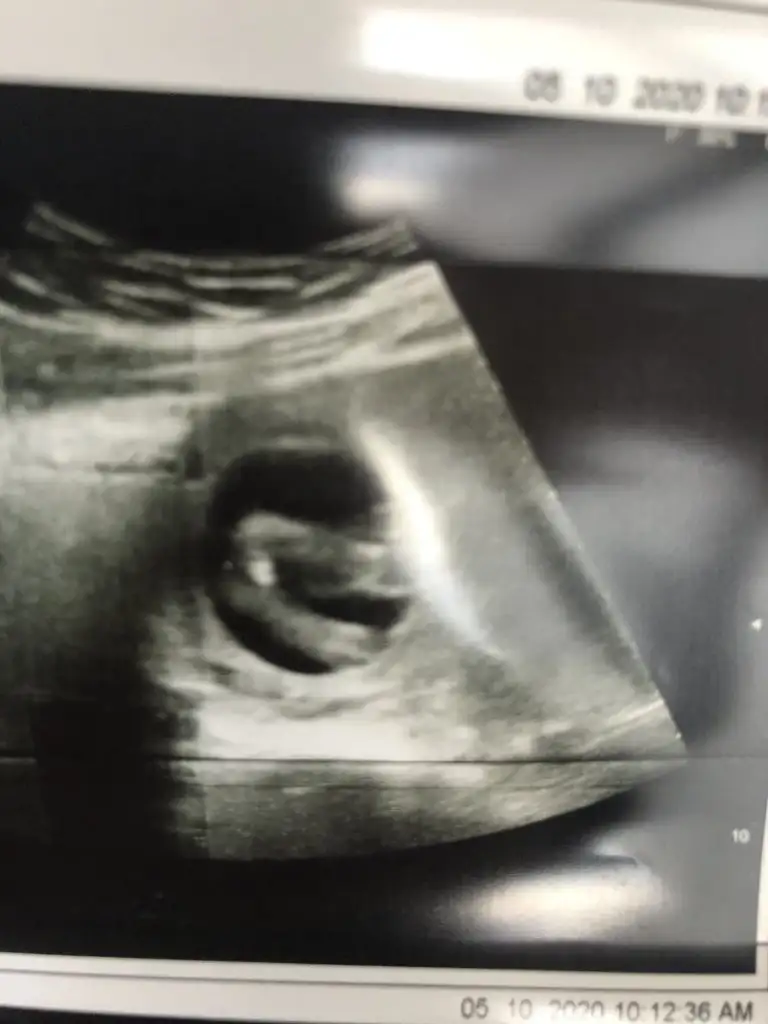

Sağlıkla gelsin cnmBugün doktor kesin kız dediIkra meyra oylamıştım zaten seni yine de söyliyim dedim çok foto attım sana hatta bak bu da son bugünki

E bu benimkiyle aynıEvet nubu karşıya bakıyor canım erkek gibi %60 ihtimal olabilir

Benimkiyle aynı görüntü senin BebekCanım bugün geldi bu ultrason doktor ölçüm de yaptı. 27 cm dedim nub açısı. O yüzden net kız da diyemem erkek de dedi. Senin yorumun nedir?

Bak Dr ne demiş canımBenimkiyle aynı görüntü senin Bebek